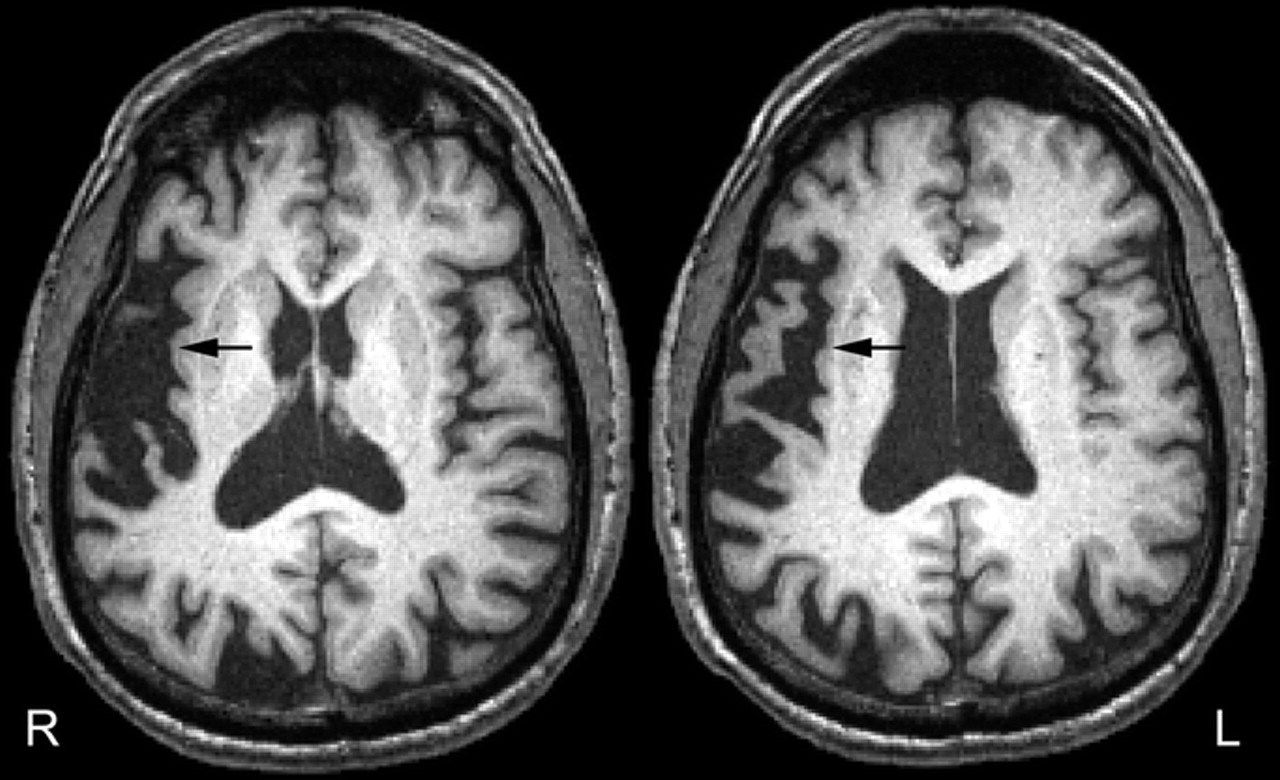

These are just a few of the strange brain disorders that have plagued a rare set of people over the years. Even many doctors know little about this rare kind of. The brain tissue between these vessels may be hardened or rigid (atrophied), full of a network of fine small the content of the website and databases of the national organization for rare disorders. Wikimedia commons has media related to diseases and disorders of the brain.